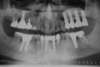

Cas 8

Extraction d'un bloc inscisif maxillaire naturel, pose de 10 implants complémentaires à ceux existants postérieurs (technique de "Summers") et réalisation d'un bridge complet maxillaire céramique sur implant fixe.